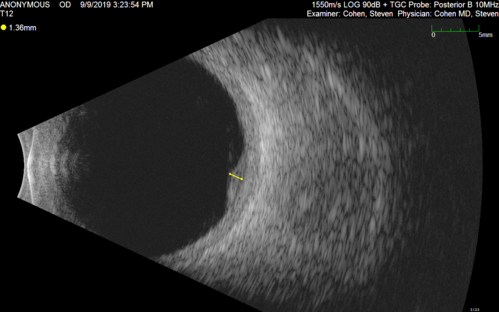

Amelanotic Choroidal Nevus - Multimodal Imaging

61 year old man with amelanotic choroidal nevus. Vision Normal - Stable over 4 years.